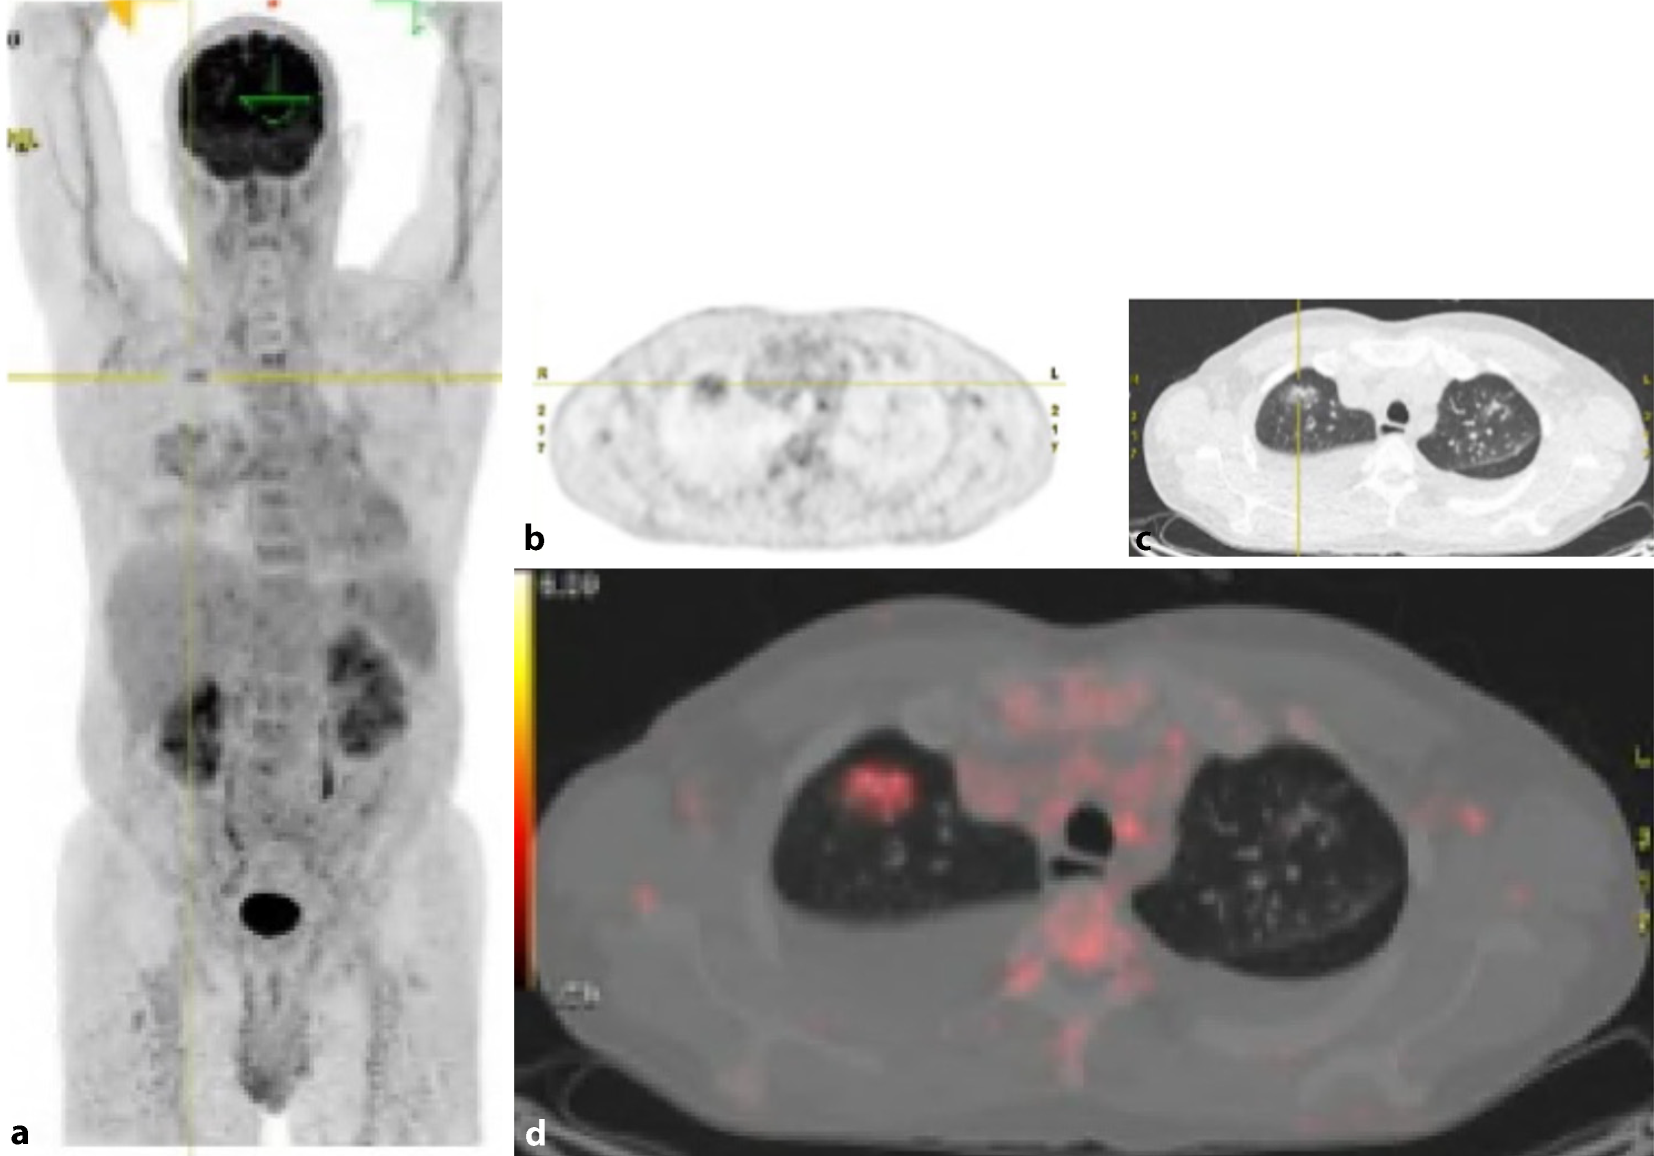

In der Histologie der Lungen- und Lymphknotenbiopsie wurden keine Neoplasien, Granulome oder Hinweise auf eine Castleman-Erkrankung beobachtet, die Befunde waren passend für eine organisierenden Pneumonie. Drei Wochen nach Beginn des Fiebers entwickelte der Patient plötzlich starke Bauchschmerzen, mit klinisch bretthartem Abdomen ohne äußere Blutungsstigmata mit Zeichen eines hämorrhagischen Schocks bei Blutdruckabfall auf systolisch 45 mm Hg, Tachykardie, kalte Peripherie und Anämie (Hb 50 g/l). Eine notfallmäßig durchgeführte abdominale CT-Untersuchung ergab eine perakute abdominale Blutung aus der linken Niere, die sich in das Retroperitoneum und in die Beckenregion ausbreitete (Abb. 2). Zudem wurde ein Verschluss der Arteria lienalis mit nahezu aufgehobener Perfusion der Milz festgestellt und weitere multiple Aneurysmata der abdominalen Arterien (z. B. eines intrapankreatischen Arterienasts und entlang der pankreatikoduodenalen Arkade) im Sinne einer fulminanten generalisierten Arteriopathie. Die konventionelle Notfallangiographie zeigte neben den Aneurysmen der Nierenarterienäste auch mehrere perlschnurartige Gefäßkaliberirregularitäten. Ein rupturiertes Aneurysma/Pseudoaneurysma, das von einem Ast der linken inferioren Nierenarterie ausging, wurde als Ursache der Blutung identifiziert und mittels Coiling des aneurysmatragenden Nierenarterienasts ausgeschaltet. Die Blutung konnte so gestoppt werden (Abb. 2). In Zusammenschau der Befunde stellten wir die Diagnose einer Polyarteriitis nodosa mit einer Gefäßruptur, intraabdominellen Blutung und einem hämorrhagischen Schock. Therapeutisch wurde mit Methylprednisolon intravenös begonnen (500 mg/Tag über 6 Tage). Jedoch kam es bereits am 4. Tag zu einer erneuten arteriellen Blutung, die notfallmäßig mit einem Coiling eines peripheren Asts der A. colica dextra versorgt werden musste (Abb. 3). Angiographisch demarkierten sich weitere Aneurysmen und perlschnurartige Gefäßkaliberirregularitäten der abdominellen Arterien z. B. im Leber- und Nierenhilus links und in der pankreatikoduodenalen Arkade. Nach klinischer Stabilisierung erfolgte eine Umstellung auf Prednison 1 mg/kg Körpergewicht und zusätzlich der Beginn mit Cyclophosphamid. Hierunter wurde ein Rückgang des CRP und der BSR festgestellt. Der Patient erhielt insgesamt 12 (monatliche) Cyclophosphamid-Infusionen (Kumulativdosis 11,6 g), während Prednison auf 5 mg täglich reduziert wurde, was zu einer partiellen Remission der Polyarteriitis nodosa führte. Ein Mangel an Adenosin-Deaminase Typ 2 wurde nicht festgestellt. Danach wurde eine Behandlung mit Tocilizumab 8 mg/kg Körpergewicht intravenös alle 4 Wochen begonnen, die zu einer vollständigen Remission führte und das Absetzen von Prednison ermöglichte. Hierunter zeigte sich in der MRT-Angiographie ein vollständiges Verschwinden der Aneurysmata und Pseudoaneurysmata innerhalb der gastrointestinalen und renalen Arterien (Abb. 4).

Abb. 3

ab Abdominelle CT-Angiographie in arterieller Phase. cd DSA-Angiographie im Rahmen des notfallmäßigen Coilings eines peripheren Asts der A. colica dextra bei relevanter aktiver arterieller unterer GI-Blutung. Zudem sind weitere Aneurysmen und perlschnurartigen Gefäßkaliberirregularitäten der abdominellen Arterien zu erkennen, z. B. im Leber- und Nierenhilus links und in der pankreatikoduodenalen Arkade